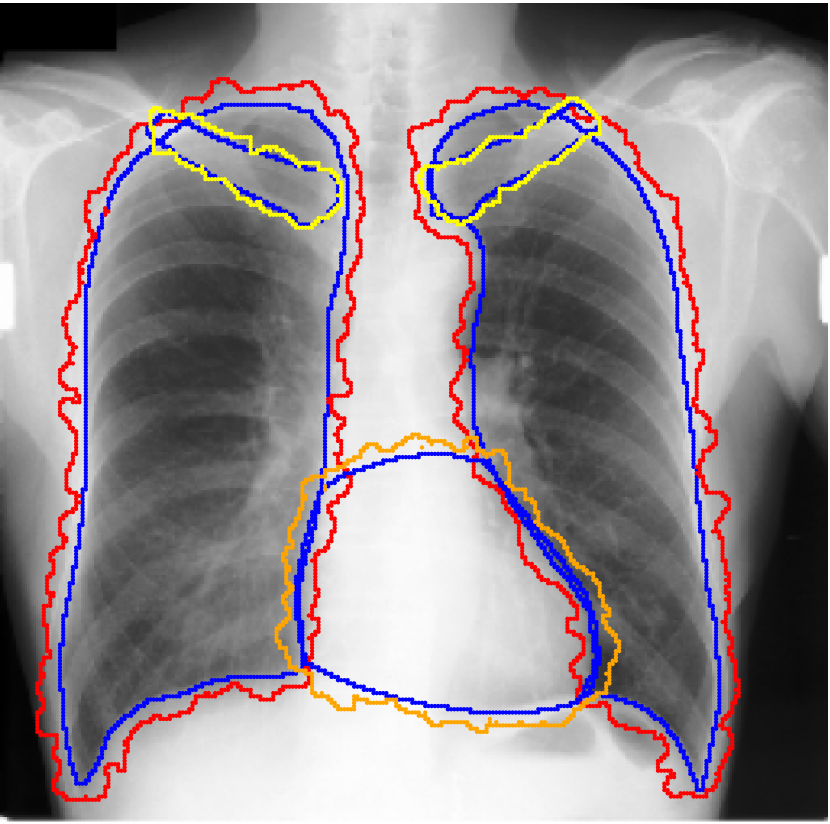

For each of these three datasets, we use three noise settings, denoted by , and . and are two settings synthesized by our Markov process with (expansion) and (shrinkage), respectively. Figure 4 shows examples of our synthesized label noise. We also include the mix of random dilation and erosion noise used by previous work (Zhu et al., 2019; Zhang et al., 2020b; a). This is achieved by randomly dilate or erode a mask with a number of pixels. Note that our Markov label noise can theoretically include this type of noise by setting . Detailed parameters for these settings are provided in the Appendix.

Real-world label noise. To evaluate with real-world label noise is challenging. We are not aware of any public medical image segmentation dataset that has both true labels and noisy labels from human annotators. Therefore, we use a multi-annotator dataset, LIDC-IDRI dataset (Armato III et al., 2015; Armato et al., 2011; Clark et al., 2013), and the coarse segmentation in a vision dataset, Cityscapes (Cordts et al., 2016). The LIDC-IDRI dataset consists of 1018 3D thorax CT scans where four radiologists have annotated multiple lung nodules in each scan. The dataset was annotated by 12 radiologists, and it is not possible to match an annotation to an expert. We use the majority voting as the true labels and the union of four annotations as noisy labels. We process and split the data exactly the same way as Kohl et al. (2018). Cityscapes dataset contains 5000 finely annotated images along with a coarse segmentation by human annotators that we use as the “noisy label”. We only focus on the ‘car’ class because (1) cars are popular objects and are frequently included in images; (2) the coarse annotation of cars is very similar to noisy annotation in medical imaging – they are reasonable distortions of the clean label without changing the topology. See Figure 4(c) for an example. The detailed settings of LIDC-IDRI and Cityscapes can be found in Appendix A.2.1.

Table 1 shows the segmentation results of different methods with synthetic noisy label settings on JSRT , ISIC 2017 and Brats 2020 dataset. Note that QAM cannot be applied to Brats 2020 dataset because their network is designed for 2D only. We compare DICE score (DSC) on testing sets (against the clean labels). For each setting, we train 5 different models, and report the mean DSC and standard deviation. In and , where biases show up in noisy labels, the proposed method outperforms the baselines by a big leap in total case. The compared methods, however, only work when little bias is included, like . is equivalent to setting in our Markov model, resulting in . We also test the proposed method on real-world label noise, results shows in Table 2. Figure 5 shows examples of label correction results. We provide more qualitative results in the Appendix A.4.